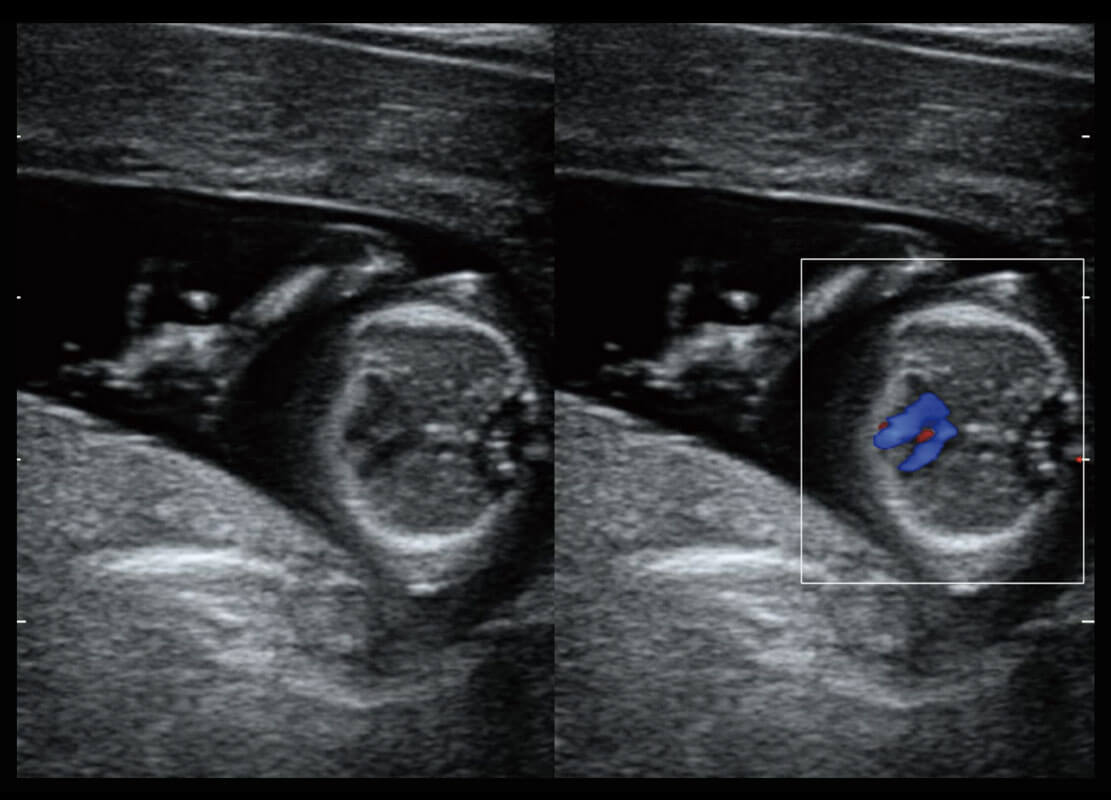

胎心筛查

P60搭载一系列胎儿心脏成像技术,实现精细的胎儿心脏评估。

• 四腔心血流